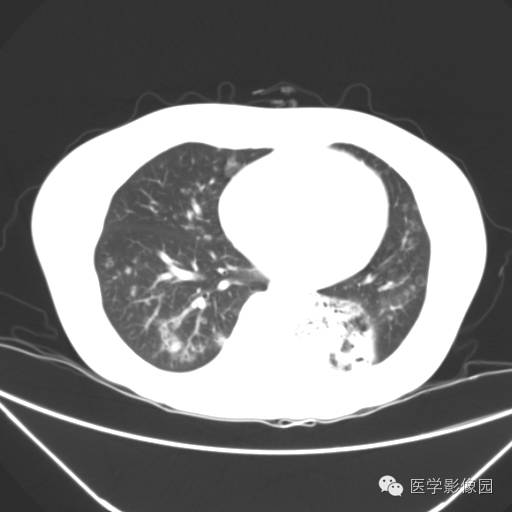

肺叶实变性支气管肺泡癌1例CT影像表现